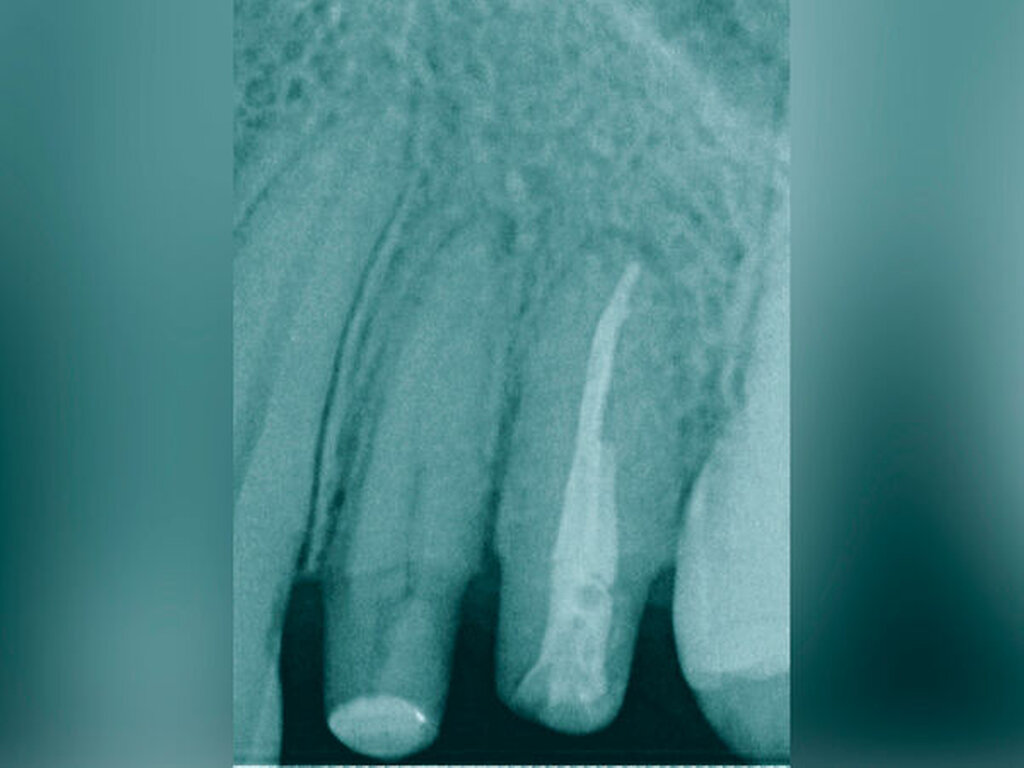

Traumatisierte Zähne mit tiefen, bis zum Alveolarknochen reichenden Defekten gelten als schwer zu restaurieren. In der Traumatologie betrifft dies Kronen-Wurzel-Frakturen oder zervikale Wurzelquerfrakturen. Zähne mit kariesbedingt hohem koronalem Zahnhartsubstanzverlust gehören ebenfalls dazu. Eine sichere Trockenlegung für den präendodontischen Aufbau und eine dichte Kofferdamanwendung sind bei derartig massiv geschädigten Zähnen kaum möglich. Adäquate endodontische Maßnahmen wären somit kaum durchführbar. Zudem gestalten sich sowohl direkte Kompositaufbauten als auch indirekte Versorgungen äußerst schwierig. Wird mit einem krestal gelegenen Restaurationsrand die biologische Breite unterschritten, verursacht dies chronische Entzündungsprozesse. Zudem ist bekannt, dass bei Überkronungen endodontisch behandelter Zähne ein „ferrule-design“ von 2 mm in gesunder Zahnhartsubstanz erzielt werden sollte [Naumann et al., 2018]. Dies sichert eine stabile koronale Restauration und vermeidet maßgeblich den frühzeitigen Retentionsverlust von Zahnersatz. Liegen Defekte vor, die eine Restauration nur unzuverlässig ermöglichen, kann eine Extrusion der Zahnwurzel sinnvoll sein. Hierbei wird der Bereich des tiefsten Zahndefekts durch die Koronalverlagerung möglichst weit iso- oder sogar supragingival positioniert, um somit eine sichere Restaurationsfähigkeit erzielen zu können. Die restaurative Versorgung bei Frontzähnen umfasst abhängig vom Ausmaß der koronalen Destruktion die direkte adhäsive Technik mittels Kompositfüllung oder laborgefertigtem Zahnersatz.

Bei der chirurgischen Extrusion (Synonym: intra-alveoläre Transplantation) wird der betroffene Zahn oder die betroffene Wurzel chirurgisch weiter koronal positioniert, um die Anfertigung einer adäquaten Restauration zu ermöglichen. Ihr biologisches Prinzip ist eingehend beschrieben worden mit guten Erfolgen im Tiermodell [Oikarinen et al., 1996] und in der klinischen Anwendung [Caliskan et al., 1999; Das und Muthu, 1999; Krug et al., 2018]. Die Technik wird bisher kaum in der zahnärztlichen Praxis angewendet, vermutlich aufgrund der begrenzten Vorhersagbarkeit, einen schwer kompromittierten Zahn oder eine Zahnwurzel erhalten zu können, wenn auf konventionelle Art und Weise extrahiert wird. Zum einen besteht das Risiko, durch die Extraktion eine Zahnfraktur zu verursachen, die den Zahnverlust zur Folge hat. Zum anderen führt die Anwendung von Luxatoren, Elevatoren oder Periotomen zu einer Aufdehnung der Alveole sowie zu Schäden am parodontalen Gewebe und gegebenenfalls an der Zahnwurzel selbst. Die Herausforderungen bei einer Zahnmobilisation für eine chirurgische Extrusion bestehen darin, weiteren Schaden an den Strukturen von Zahnhartsubstanz, Knochen und parodontalem Ligament zu vermeiden. Gelingt dies, können deren Hauptrisiken wie Zahnfraktur und progressive Wurzelresorption minimiert werden [Elkhadem et al., 2014].

Eine weitere Möglichkeit, tief zerstörte Zähne möglichst schonend chirurgisch zu extrudieren, basiert auf axialen Zugsystemen (Abbildungen 2 bis 4). Diese erscheinen vorteilhaft bei sehr schwierigen Fällen, zum Beispiel bei Zähnen mit fehlendem Ansatzpunkt für die Zange sowie bei langen oder sehr ovalen Wurzeln. Axiale Zugsysteme ermöglichen die Übertragung von Zugkräften auf die Zahnwurzel, ohne die Alveole unnötig zu dehnen. Dazu wird eine spezielle Schraube in den Wurzelkanal eingebracht und das Gewinde der Schraube für eine ausreichende Friktion fingerfest eingedreht. An diese Schraube wird ein gerätespezifisches Zugsystem angelegt. Durch rein axial wirkende Zugkräfte werden traumatische Effekte auf Knochen und Wurzeloberfläche während der Zahnmobilisation minimiert. Gegebenenfalls können feine Luxatoren vorsichtig unterstützend eingesetzt werden. Im Tiermodell wurde an extrahierten und wieder replantierten Zähnen mit ovalem Querschnitt gezeigt, dass der Verlust von Zementoblasten auf der Wurzeloberfläche geringer ist, wenn ein axiales Zugsystem anstatt einer Extraktionszange verwendet wird.

Die wesentliche technische Komplikation stellt das unverhältnismäßige Erweitern des Wurzelkanals für die Retention des Zughilfsmittels – zum Beispiel der Benex-Schraube – dar. Der Behandler sollte hier unter besonderer Vorsicht den bereits instrumentierten und präparierten (vorgegebenen) Wurzelkanal als Bohr- und Zugpfad für die Extrusion nutzen. Auf die Schonung der gesunden Zahnhartsubstanz muss geachtet werden. Die Bohrachse für die Ausrichtung der Zugschraube muss mit dem koronal gelegenen Hauptpfad des Wurzelkanals übereinstimmen. Zudem ist für das Erzielen einer ausreichenden Retention der Schraube ein gewisses Maß an Feingefühl und Taktilität vom Behandler erforderlich. Eine neue Schraube erfüllt die Vorbedingung eines schneidfreudigen Gewindes und damit eines guten Halts im Zahn am besten.